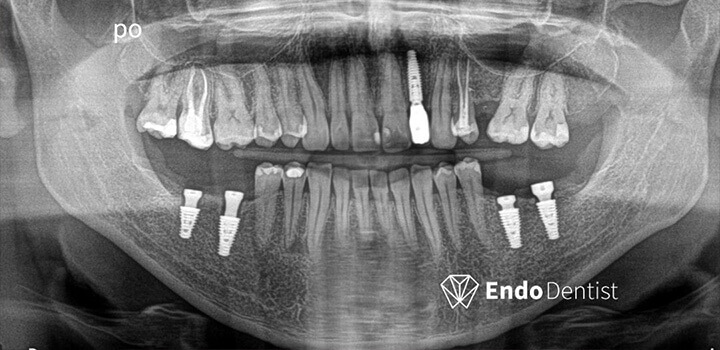

Efekty, które mówią same za siebie